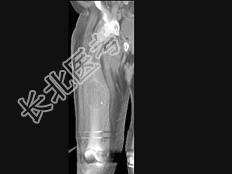

- 单项选择题男,18岁, 右股骨肿瘤术后,出现大腿中段疼痛, 夜间尤甚,结合CT图像, 最可能的诊断是 ( )